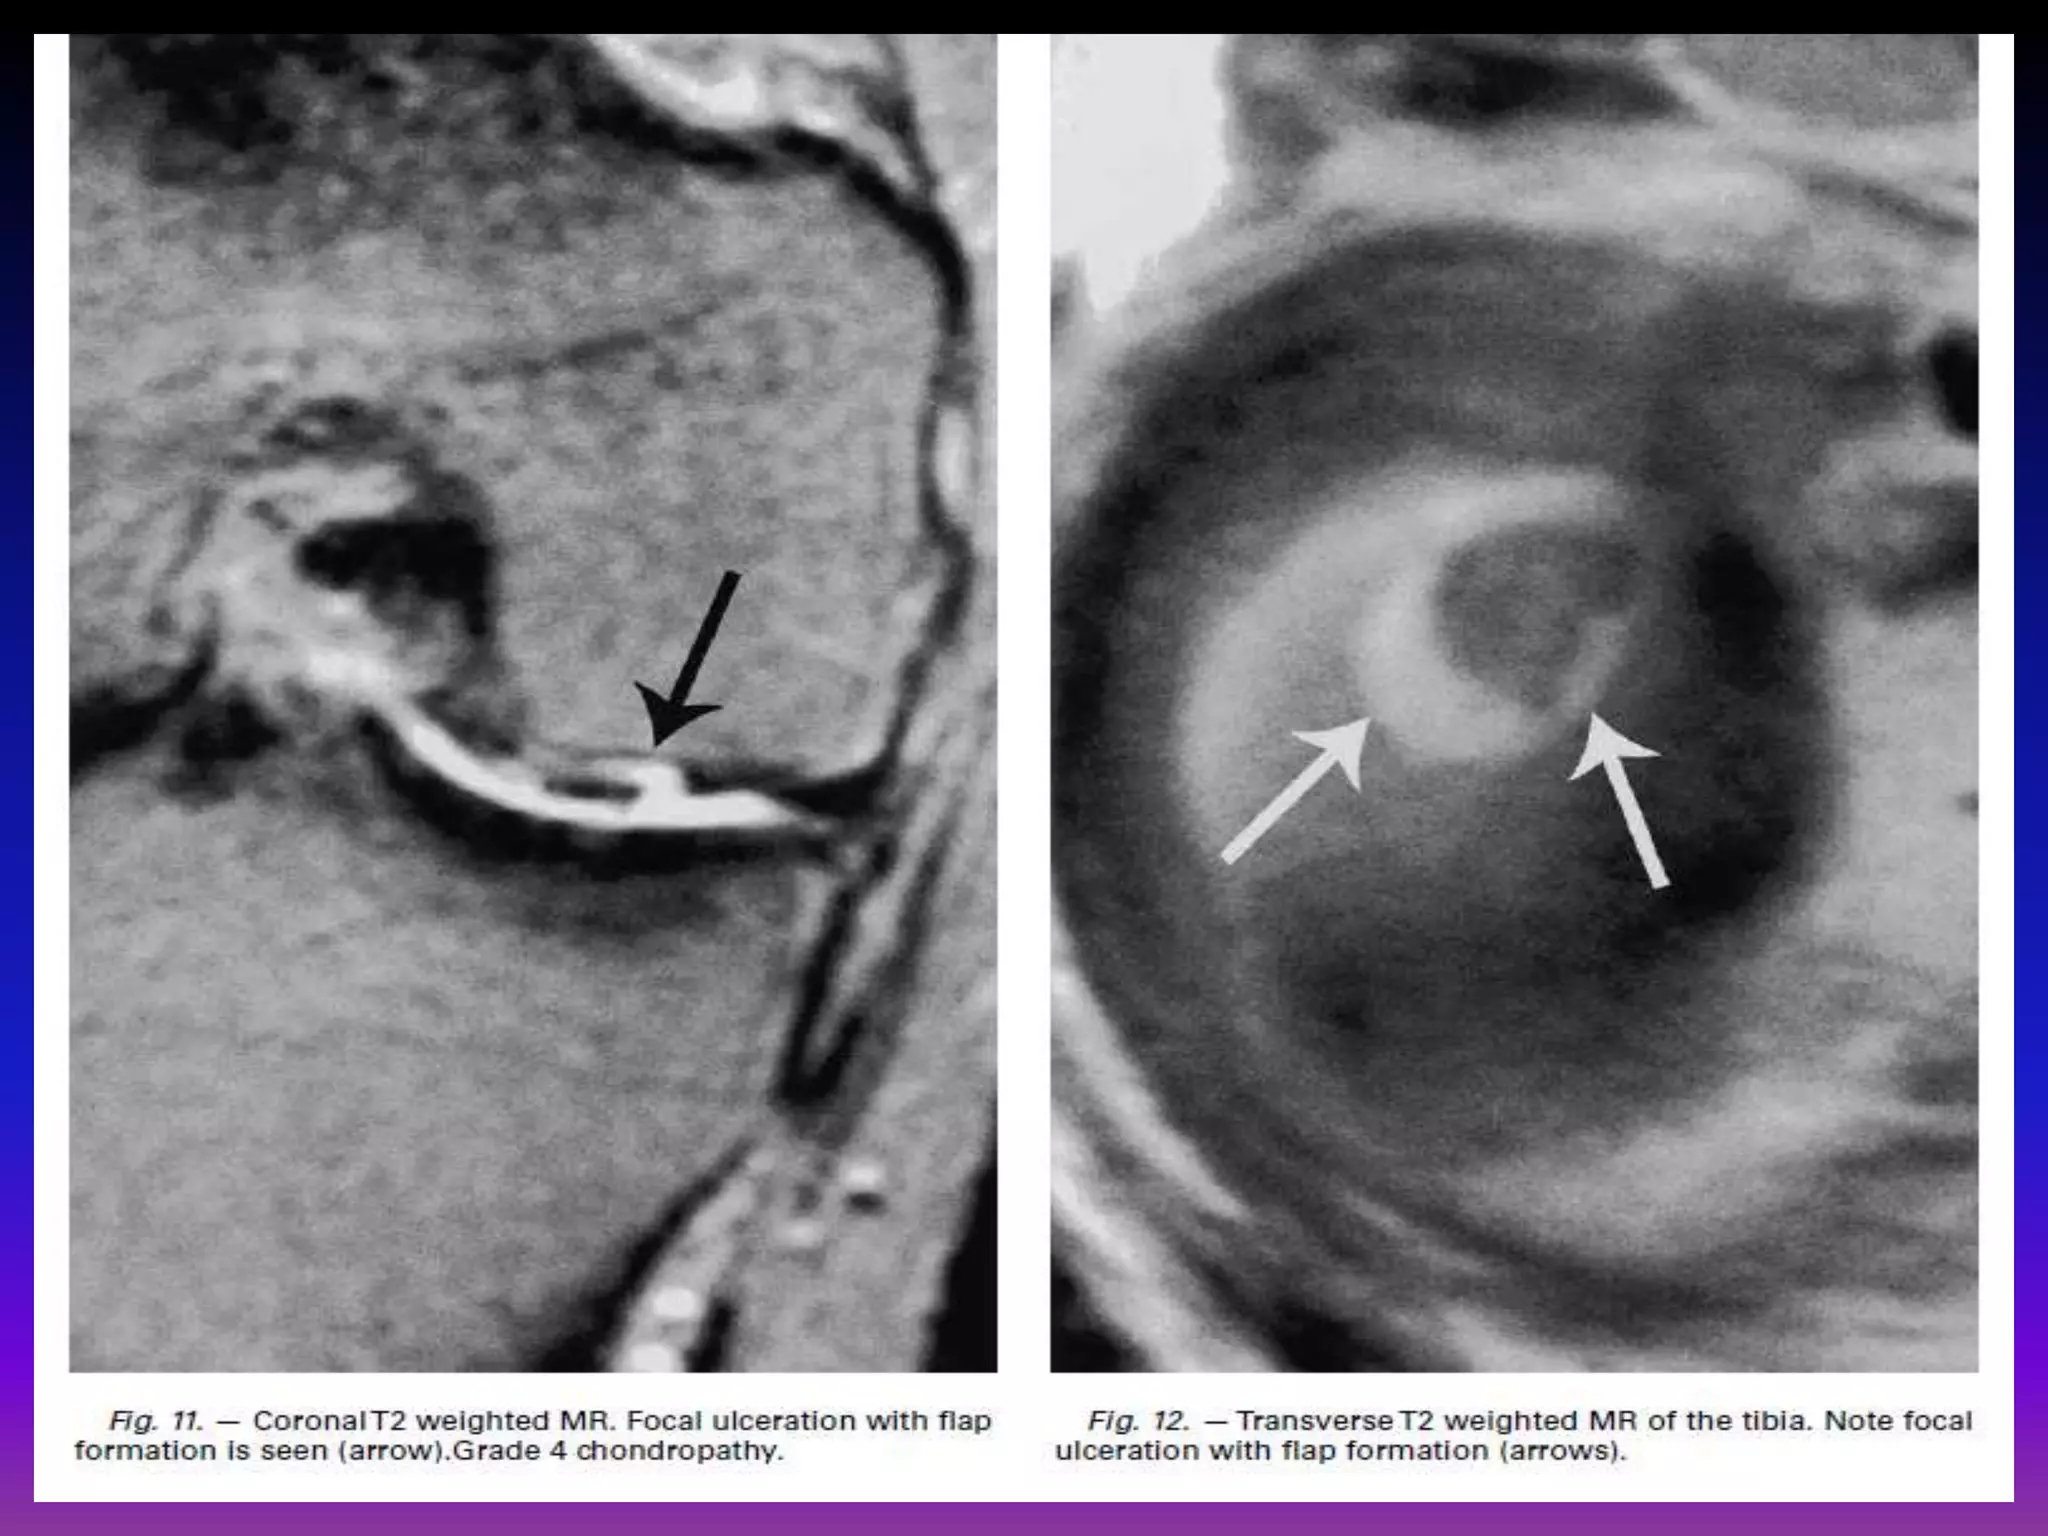

grade IV.

Full thickness cartilage loss with underlying bone reactive changes

arthroscopically : cartilage destruction with exposed subchondral bone.

Transverse CT arthrographicimage. several patellar fissures are seen extending to subchondral bone, compatible with grade 4 chondropathy. Transverse proton density weighted MR with FS of patella. Fissures are seen (thin arrows) extending to subchondral bone compatible with grade 4 chondropathy. Patchy subchondral edema is also evident (bold white arrow).

Full thickness chondrallesion , exposed subchondral bone.